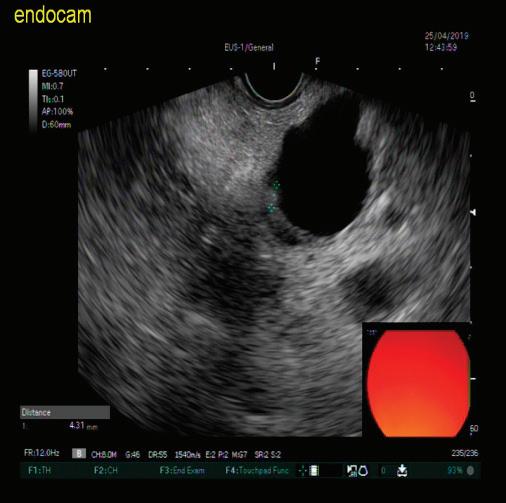

КИСТИ НА ПАНКРЕАСАЗНАЧЕНИЕ, ДИАГНОСТИЧНИ ДИЛЕМИ И ИНДИКАЦИИ ЗА ХИРУРГИЯ

48 КИСТИ НА ПАНКРЕАСАЗНАЧЕНИЕ, ДИАГНОСТИЧНИ ДИЛЕМИ И ИНДИКАЦИИ ЗА ХИРУРГИЯ Н. Шумка, П. Карагьозов

2023 БРОЙ 74 03.2020 СПЕЦИАЛИЗИРАНО ИЗДАНИЕ ЗА ЛЕКАРИ WWW.MEDMAG.BG БРОЙ 74 03.2020 БРОНХОДИЛАТАТОРИТЕ С ДЪЛГО ДЕЙСТВИЕ ПРИ ЛЕЧЕНИЕ НА СТАБИЛНА ХОББ СТР. 4 ХРОНИЧЕН РИНОСИНУИТ С НАЗАЛНА ПОЛИПОЗА И ЕОЗИНОФИЛНО ВЪЗПАЛЕНИЕ СТР. 24 КИСТИЧНИ ПАНКРЕАСНИ НЕОПЛАЗМИ СТР. 62